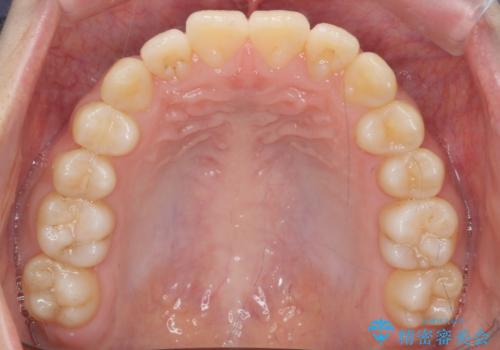

前歯のがたつき 部分矯正でコストダウンしながら、かみ合わせも治療

- 前歯のがたつきを気にして来院。

左下の小臼歯が捻転し、反対咬合になっていました。

先にワイヤーで部分矯正を行ってから、インビザラインの部分矯正を行いました。

先に難しい部分をワイヤー矯正することで、インビザラインの部分矯正コースで短期間で予算も抑えて確実に治すことができます。